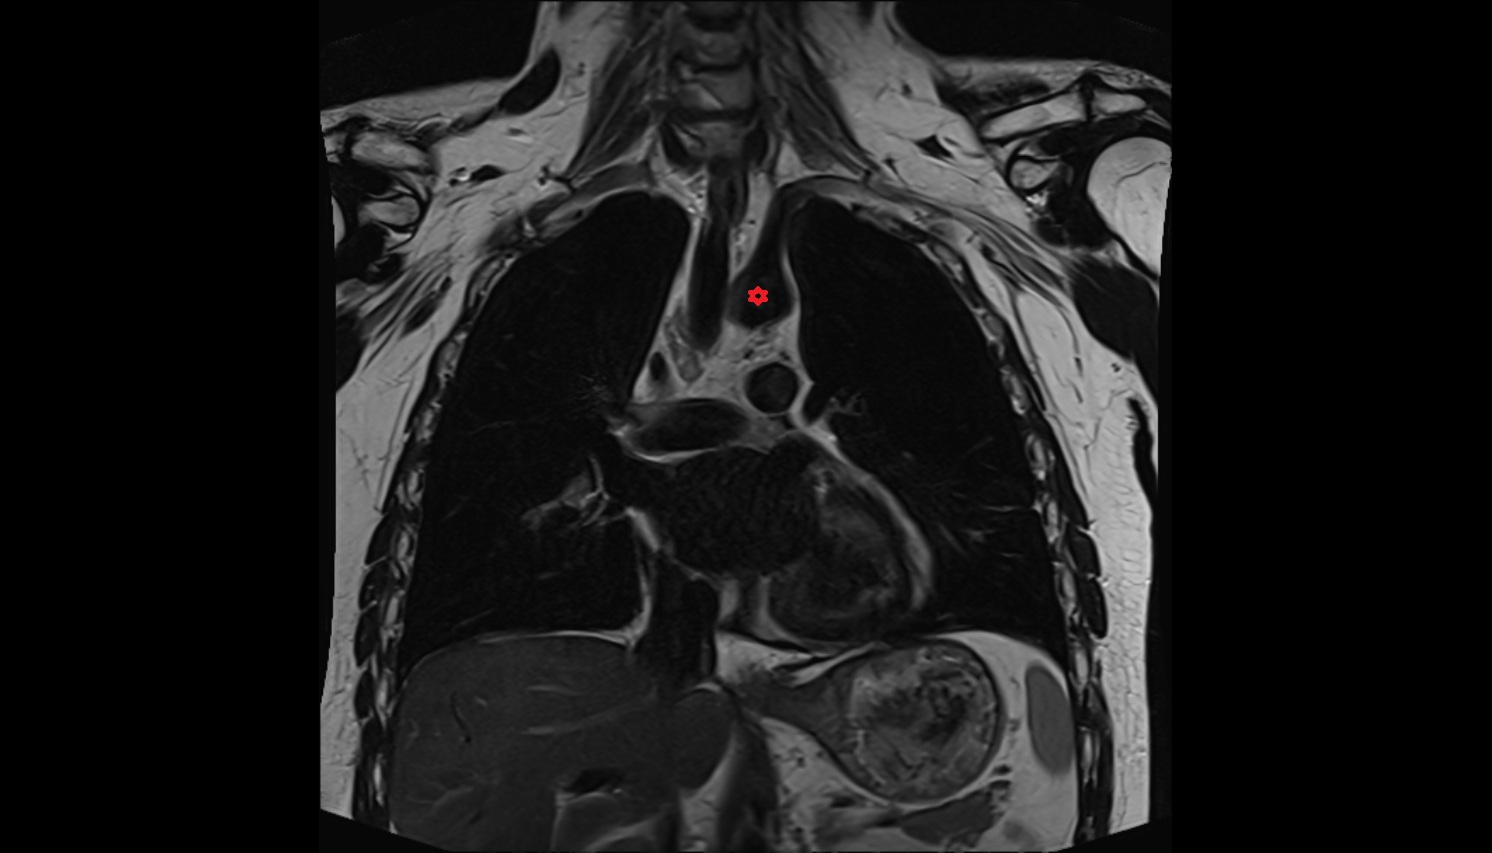

- Thoracic part of esophagus

- Trachea

- Heart

- Ascending aorta

- Arch of aorta

- Descending thoracic aorta

- Thymus